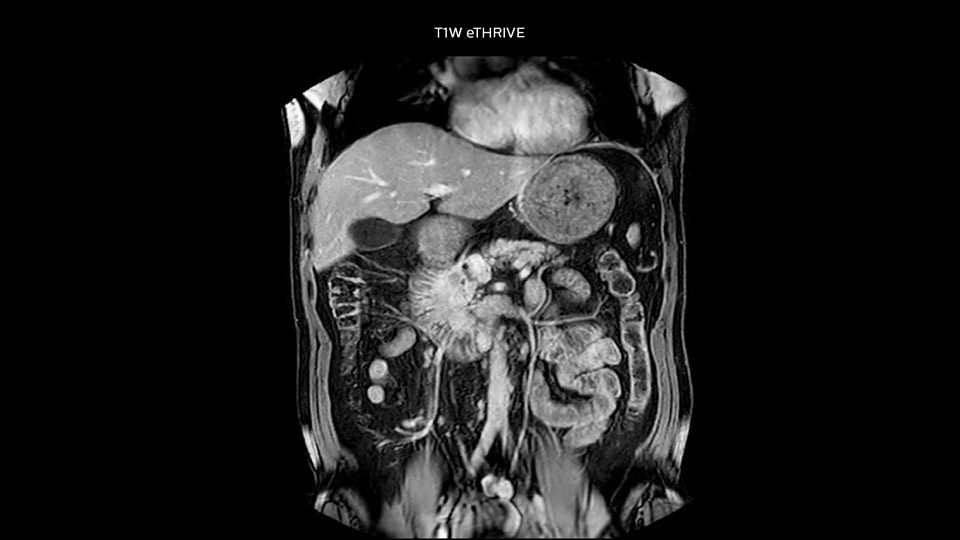

“Our liver exams are quite fast,” says Dr. Baumann. “If the patient tolerates it, we use an arms-up position to reduce the FOV and speed up the exam with dS SENSE.” “We acquire one transversal high resolution T2-weighted sequence with 3 mm slice thickness, for example for pancreas or liver lesions. Then we also add a T2 fat suppressed MultiVane XD SPIR sequence. We perform these two routinely in our liver imaging. We use high dS SENSE factors to significantly shorten scan times to 2-4 minutes, which can improve our protocol; it’s a very robust scan.” “We include mDIXON for the dynamic sequences because of the robust and homogeneous fat suppression we get with that. We had been using eTHRIVE, but we are now quite happy with mDIXON. Sometimes we use a medication to calm the bowels, to further improve the image quality.”

“We are more confident in our diagnosis if we don’t have to rescan the patient and compare it to other studies; this liver exam gives us good image quality in a faster time than the default system’s approach with arms down. That makes a difference for the patients, too. The shorter scan times, especially with the high dS SENSE factors, shorten the duration of the total examination. At the same time it’s more comfortable for the patient, to rest normally without holding the breath, just relaxing.”